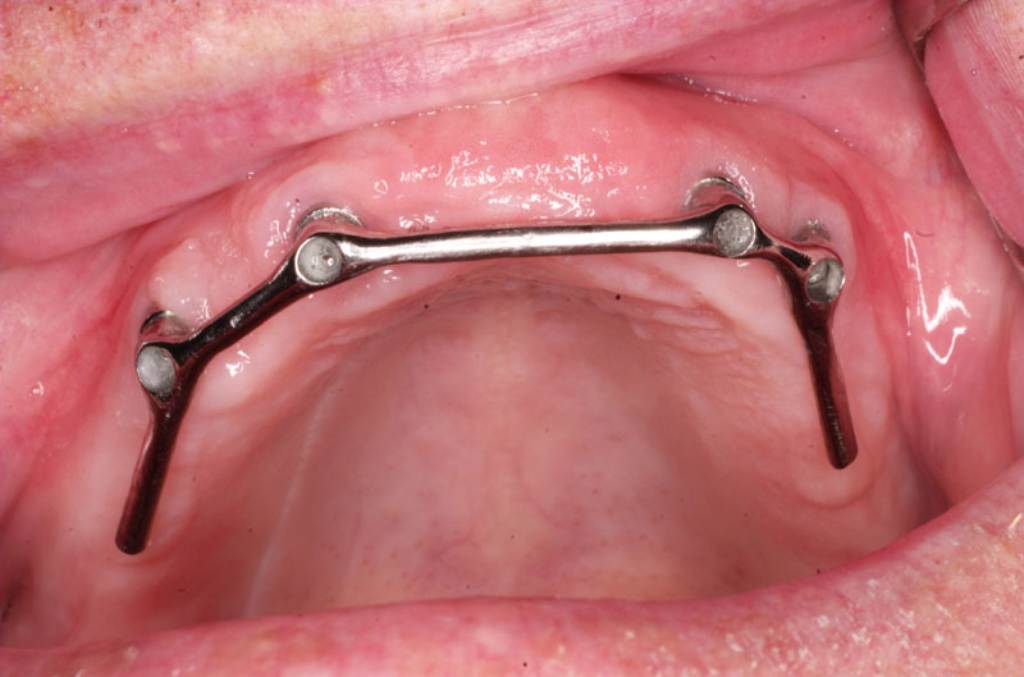

Třmeny

S pomocí zubních implantátů můžeme díky různým kotevním systémům (třmeny, kulové hlavy, Locatory) zajistit stabilitu a držení protézy nebo při použití většího počtu implantátů zhotovit pevné náhrady – můstky nalepené nebo našroubované na pevno na implantáty.